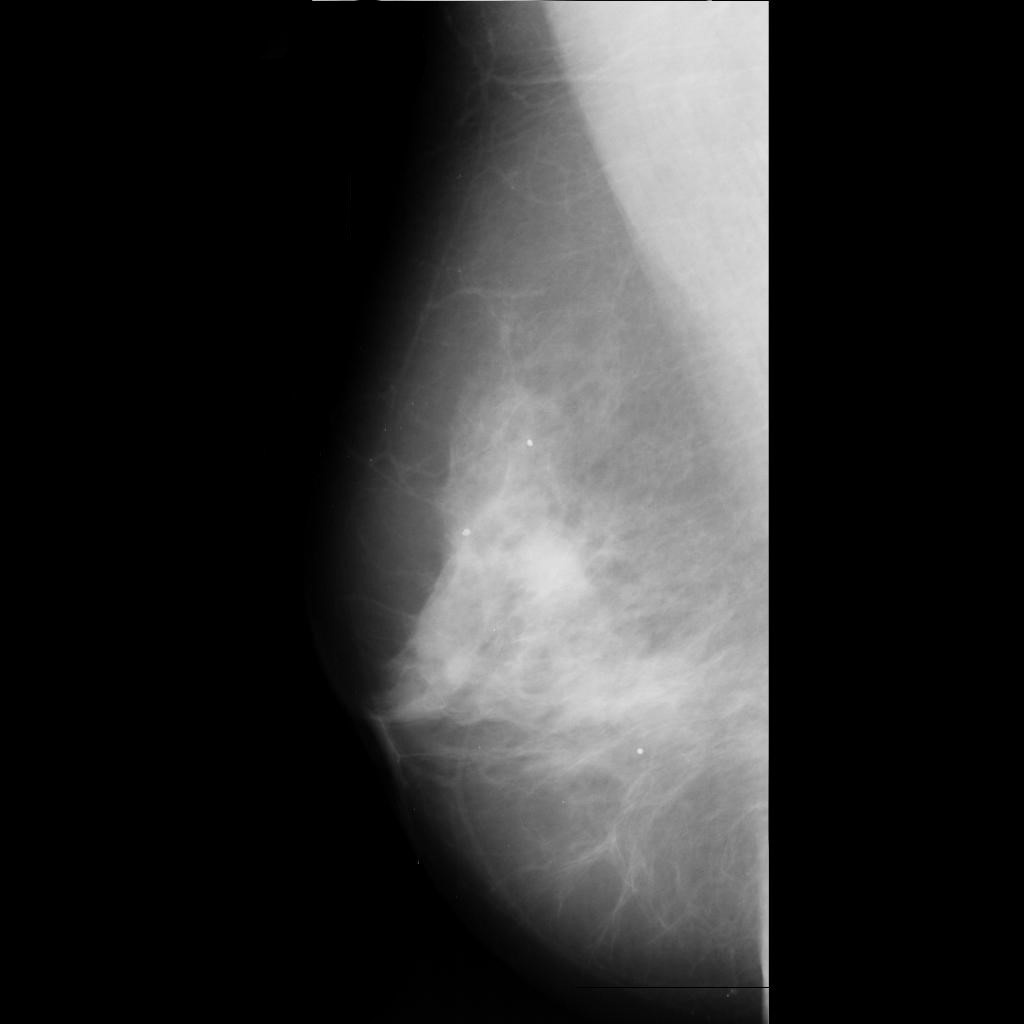

malignant